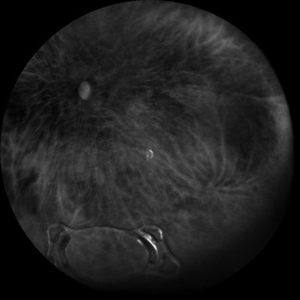

Giant Retinal Tear with Retina Detachment, Both Eyes

Fundus photograph of a 13 year-old female with giant retinal tear and retinal detachment in both eyes.

Photographer: Dr. Akansha Sharma-Retina Foundation, Ahmedabad

Condition/keywords: giant retinal tear, proliferative vitreoretinopathy (PVR)